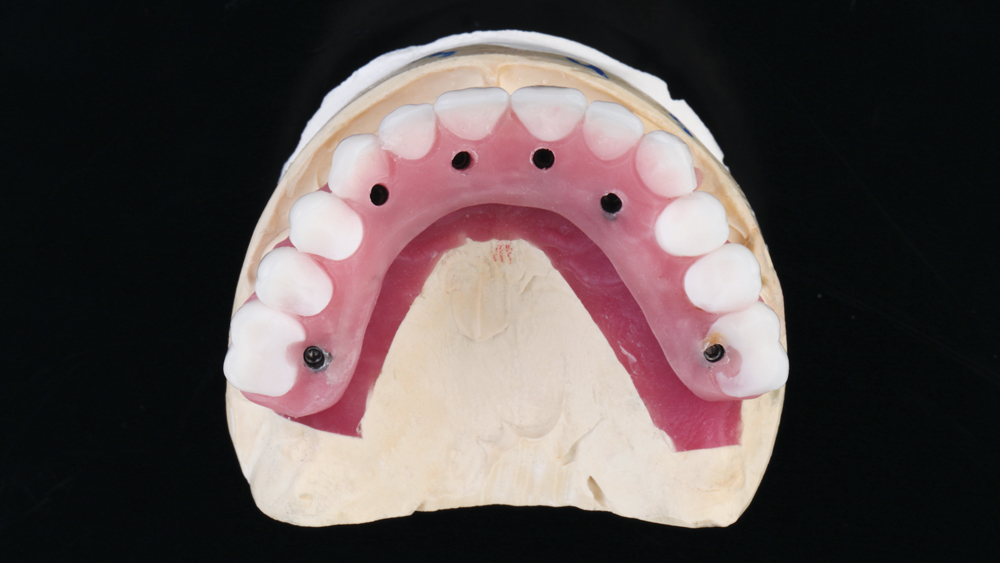

To establish the foundation needed for a screw-retained restoration and avoid fracturing the facial plate, clinicians must position the immediately placed implant against the lingual or palatal wall of the extraction socket. This is one of the reasons I designed the Hahn™ Tapered Implant (Glidewell Direct; Irvine, Calif.) with deep, sharp threads, which enable precise directional control during insertion and prevent the implant from “walking” toward the facial plate as it is threaded into place. This thread design also leads to high primary stability in all bone types, which is essential when performing the extraction with immediate implant placement procedure.1,2

Once osseointegration is complete, the BruxZir® Full-Arch Implant Prosthesis is the ideal choice for the restoration, as its monolithic construction prevents chips, stains, breakage, and dislodged or worn-down prosthetic teeth.3,4 This treatment option has helped elevate the quality of care I’m able to provide for my edentulous patients, who no longer return to my office with a broken acrylic appliance in hand.

The following case demonstrates how to immediately place implants in full-arch indications. By properly positioning the implants, maximizing primary stability and providing the most durable restoration possible, the short- and long-term needs of the patient are addressed in an efficient, predictable manner.